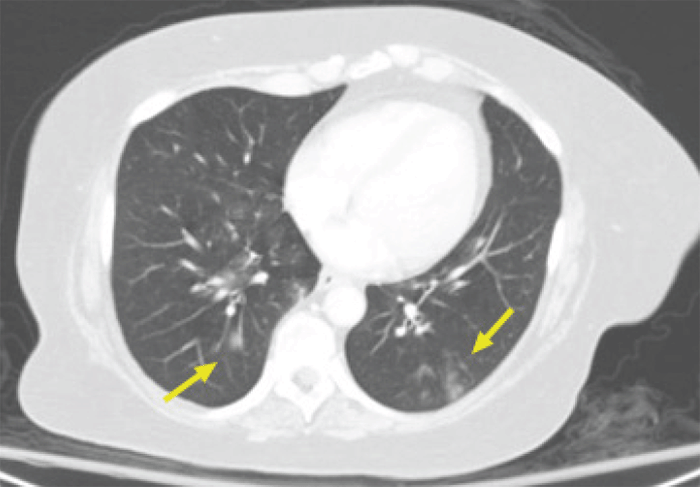

Her abdomen was soft, distended, tympanitic, nontender, with no notable hernias or scars on physical exam. Her lungs were clear to auscultation bilaterally, and there was no lymphadenopathy noted. Her right lower extremity was in a brace, and her hands were described as "agitated." ED labs were significant for WBC 19000 and slight hyponatremia of 134. Computed tomography (CT) of the abdomen and pelvis showed a partial bowel obstruction with a transition zone in the left hemiabdomen but no clear transition point (Figure 1). The distal small bowel was decompressed with no evidence of bowel ischemia or perforation. She was also noted to have nodular opacities at the bilateral lung bases (Figure 2).

Figure 2. Axial CT Abdomen with Contrast in Lung Window Showing Bilateral Lung Bases with Nodular Opacities. Published with Permission